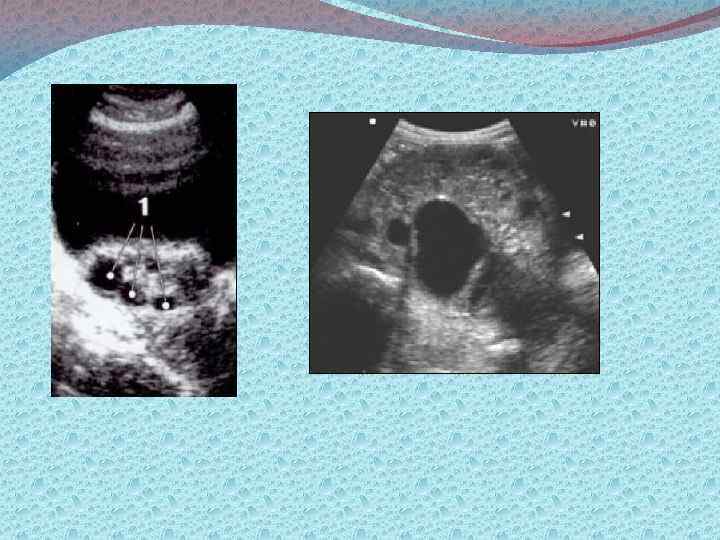

Методы диагностики: Визуализирующие: а)лучевые б)эндоскопические Лучевые: УЗИ, КТ, МРТ. Эндоскопические: лапароскопия, пункция заднего свода, забор материала для гистологического исследования. Лабораторные. Определение типов опухолевых маркеров: 1) онкофетальные и онкоплацентарные а/г (РЭА, АФП ХГЧ, ТБГ) 2) Опухолеассоциированные антигены (СА 125, СА 19 9, СА 72 4) 3) Ферменты (ПЩФ, НСЕ) 4) Гормоны (кальцитонин, эстрадиол, пролактин, ТТГ) 5) Продукты онкогенов 6) Белки острой фазы (ферритин, С реактивный белок, РЭА) 7) Биологически активные пептиды (ПГ, ГАГ, M CSF)

Стадирование злокачественных опухолей яичников: Первый этап: Физикальные методы обследования, в том числе осмотр шейки матки зеркалами; Са 125 в крови и моче; УЗИ органов брюшной полости, таза; Цитологическое исследование пунктата заднего свода влагалища Второй этап (для более точной оценки распространенности процесса, наличия метастазов): Компьютерная и магниторезонансная томография Рентгенография органов грудной клетки Цистоскопия, Внутривенная урография Сцинтография костей скелета